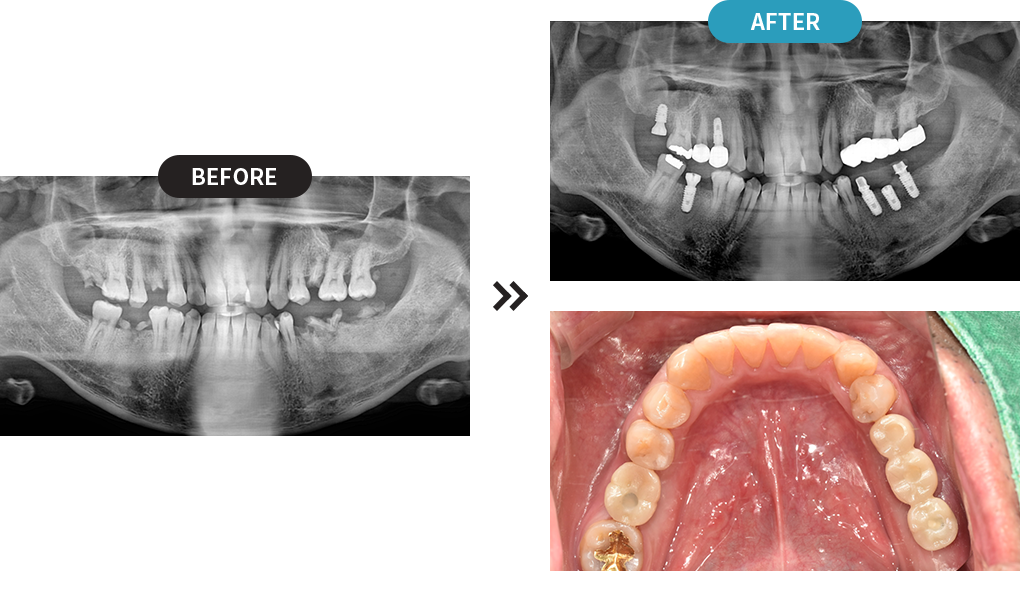

3D디지털 스캔을 활용하여 가장 안전하게 임플란트를

식립할 수 있는 위치를 0.1mm 오차까지 정확하게 계산합니다.

제작된 보철물을 모의 수술을 통해 정해진 임플란트 식립 위치에 빠르고 정확하게 식립합니다.